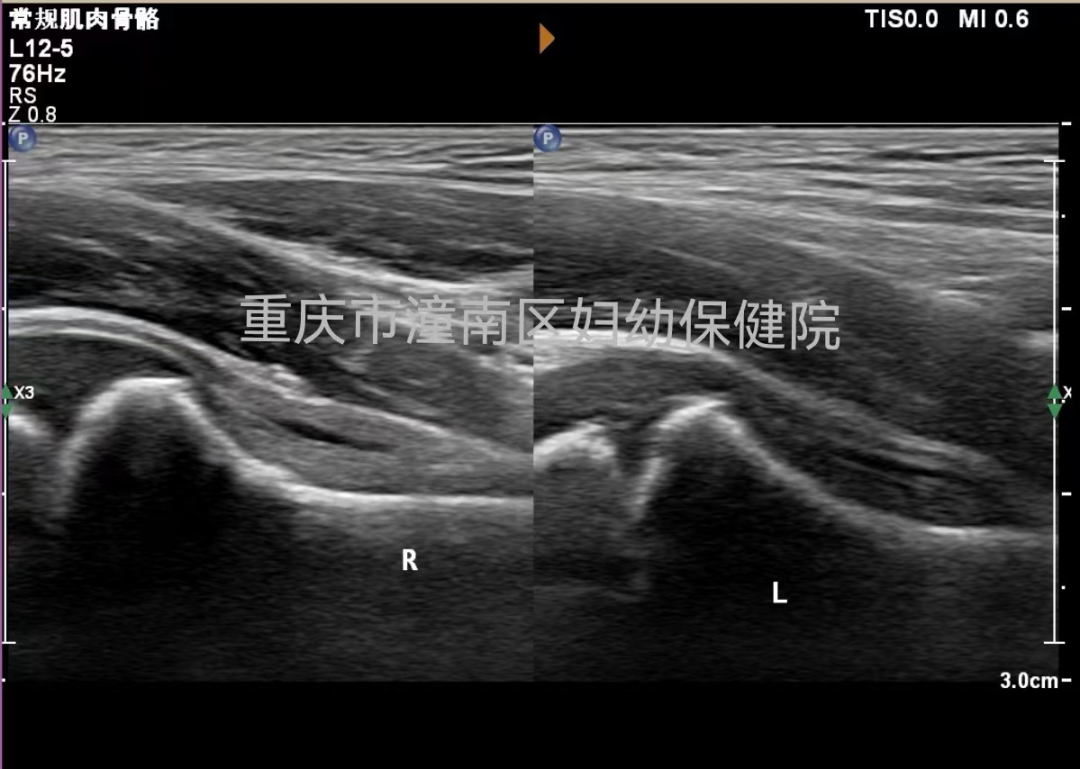

我院影像诊断科通过超声检查早期发现积液、滑膜增厚等情况,可明确诊断小儿急性髋关节滑膜炎。并且这种检查无创、快捷、无辐射。

正常滑膜